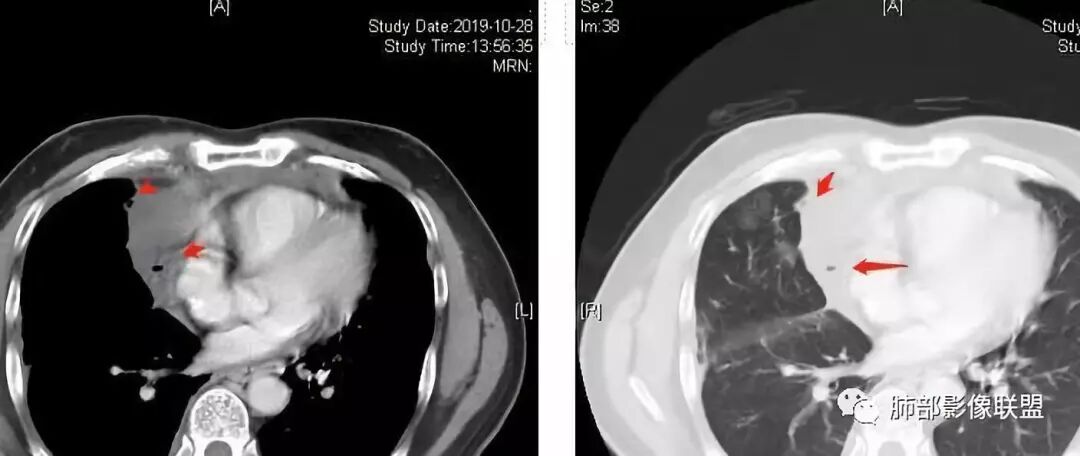

大家仔细看看积液中的游离气体;

不是支气管,是积气;是穿刺进去的;

囊内密度不一致

我认为囊张力高,积液中的气体均在周围,外侧、下方,囊内有间隔:各腔密度不一致;提示:囊腔属于前纵隔,不是包裹性积液;现在的问题:囊腔与内侧的病灶是否是一体的

肺内结节,近端支气管堵塞狭窄

整体边缘收缩,部分膨隆

炎性要考虑,但恶性不能排除